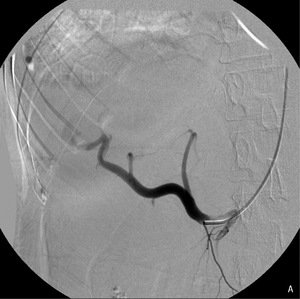

W przewlekłym zapaleniu wątroby najbardziej prawdopodobny jest mechanizm narastania nadciśnienia w wyniku powolnej zaniku drobnych naczyń krążenia wrotnego. W takich warunkach do zakrzepicy jako konsekwencji zwolnienia przepływu dochodzi rzadko – sukcesywnie rozwija się krążenie oboczne, zapewniające odpływ krwi z ominięciem zmienionego narządu. Zakrzepica żyły wrotnej częściej występuje w przebiegu zapalenia trzustki, sepsy, poważnych zaburzeń układu krzepnięcia lub marskości poalkoholowej. W opisanym przypadku przyczyną nadciśnienia wrotnego była pourazowa przetoka tętniczo-wrotna, będąca powikłaniem biopsji gruboigłowej wątroby. Częstość tego powikłania jest większa w przypadku bioptowania marskiego narządu, który jest mniej sprężysty. Przeciek w przetoce narastał powoli, dlatego dopiero po 2 latach przeciążenie objętościowe układu wrotnego spowodowało narastanie żylaków przełyku i krwawienie z górnego odcinka przewodu pokarmowego.